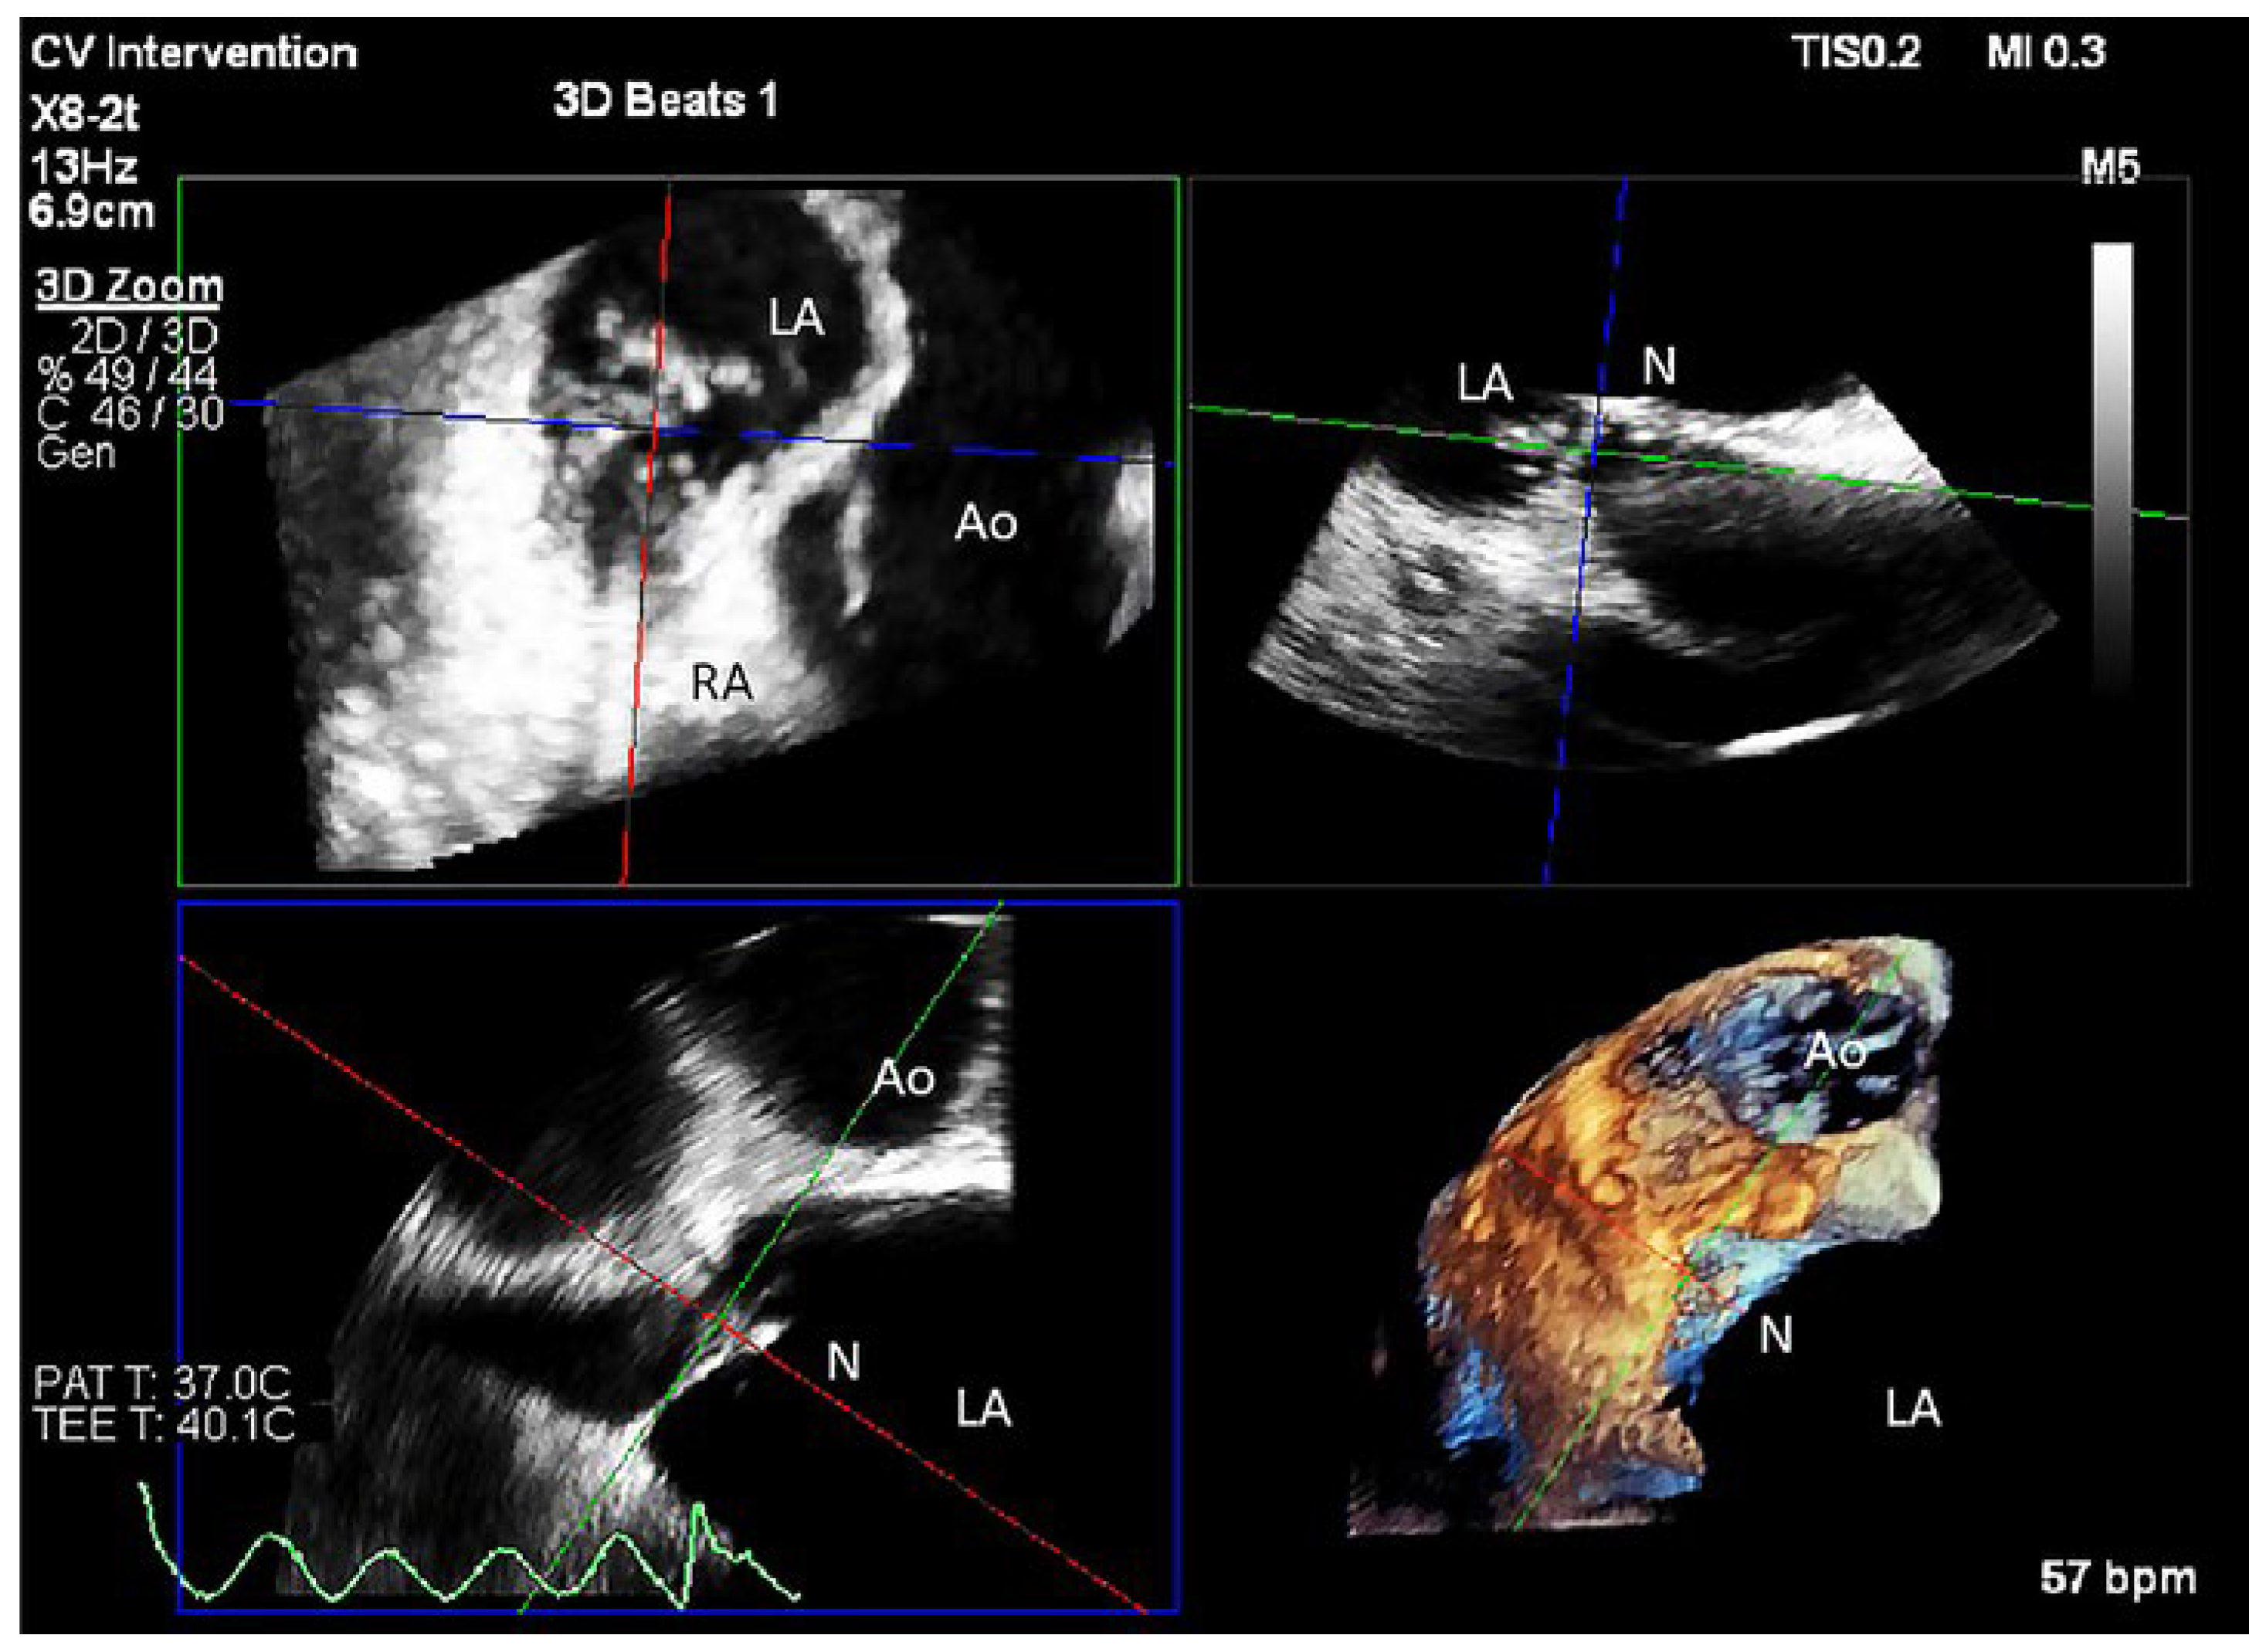

Case description